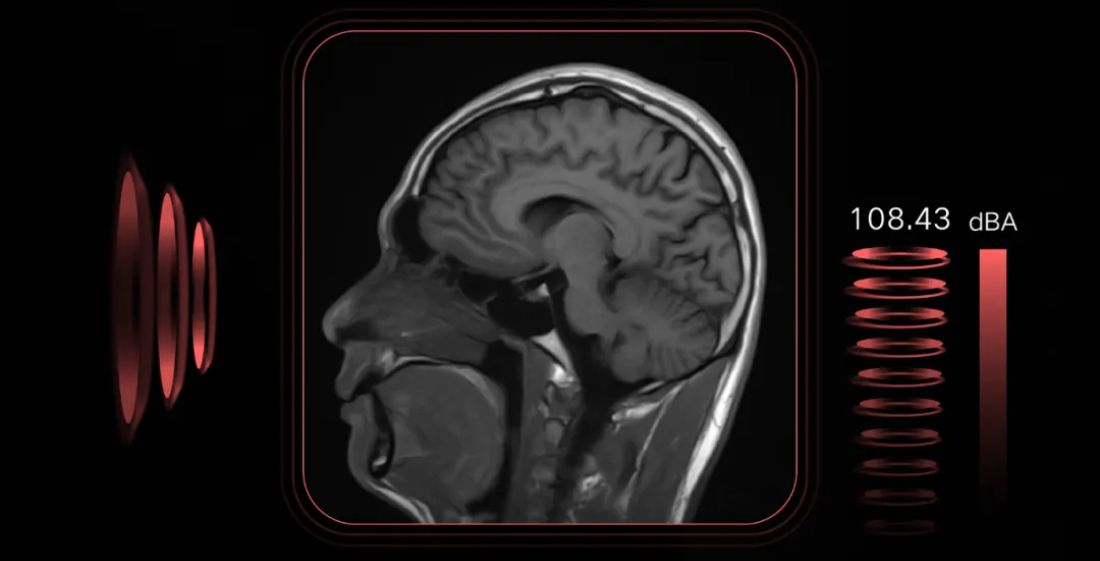

Resonancia Magnética Abierta Musculo-Esquelética: Ventajas y Usos

Conoce qué es la Resonancia Magnética sin Helio y sus ventajas en el diagnóstico médico moderno. ¡Innovación en tecnología de salud!